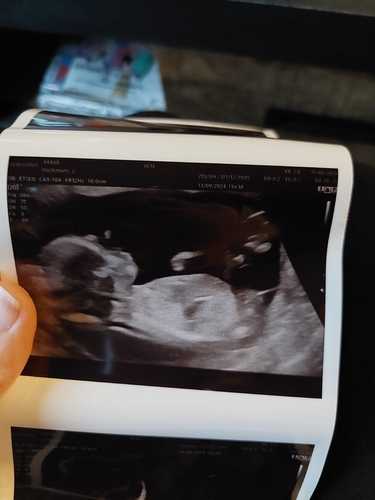

Is het op deze echo's te zien? Hier was ik 13+5

Alleen linksboven, maar wel duidelijk 💙🤭